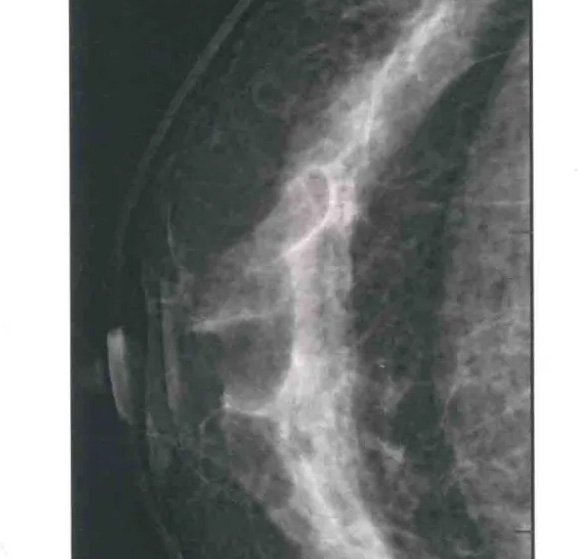

二、圖像顯示要求,含乳腺的基底部及內(nèi)外側(cè)乳腺組織,需要顯示胸肌前緣或胸壁。頭尾位與內(nèi)外斜位乳頭后線長度差≤1厘米;顯示實質(zhì)后的乳腺組織,乳頭位于切線位,乳腺組織重疊;雙側(cè)乳腺頭尾位照片相對放置,則兩側(cè)乳腺呈球形;影像密度和對比度良好,能顯示0.1毫米細小鈣化,清晰沒有偽影異物、運動偽影和切割偽影等。